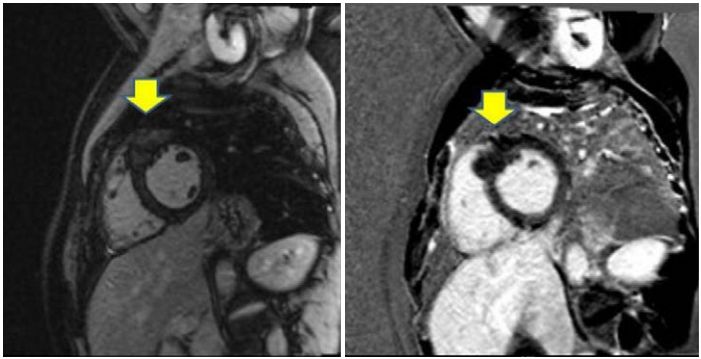

该患者有吸烟史,加上气短的临床表现,鉴别诊断包括冠状动脉疾病。患者的超声心电图未发现室壁运动异常,除外了心梗引起的Q波。随后的心脏磁共振检查显示不成比例的间隔肥厚和晚期钆增强(图3)。确定诊断为肥厚型心肌病。

图3 心脏磁共振显示前间壁基底部局灶性肥厚